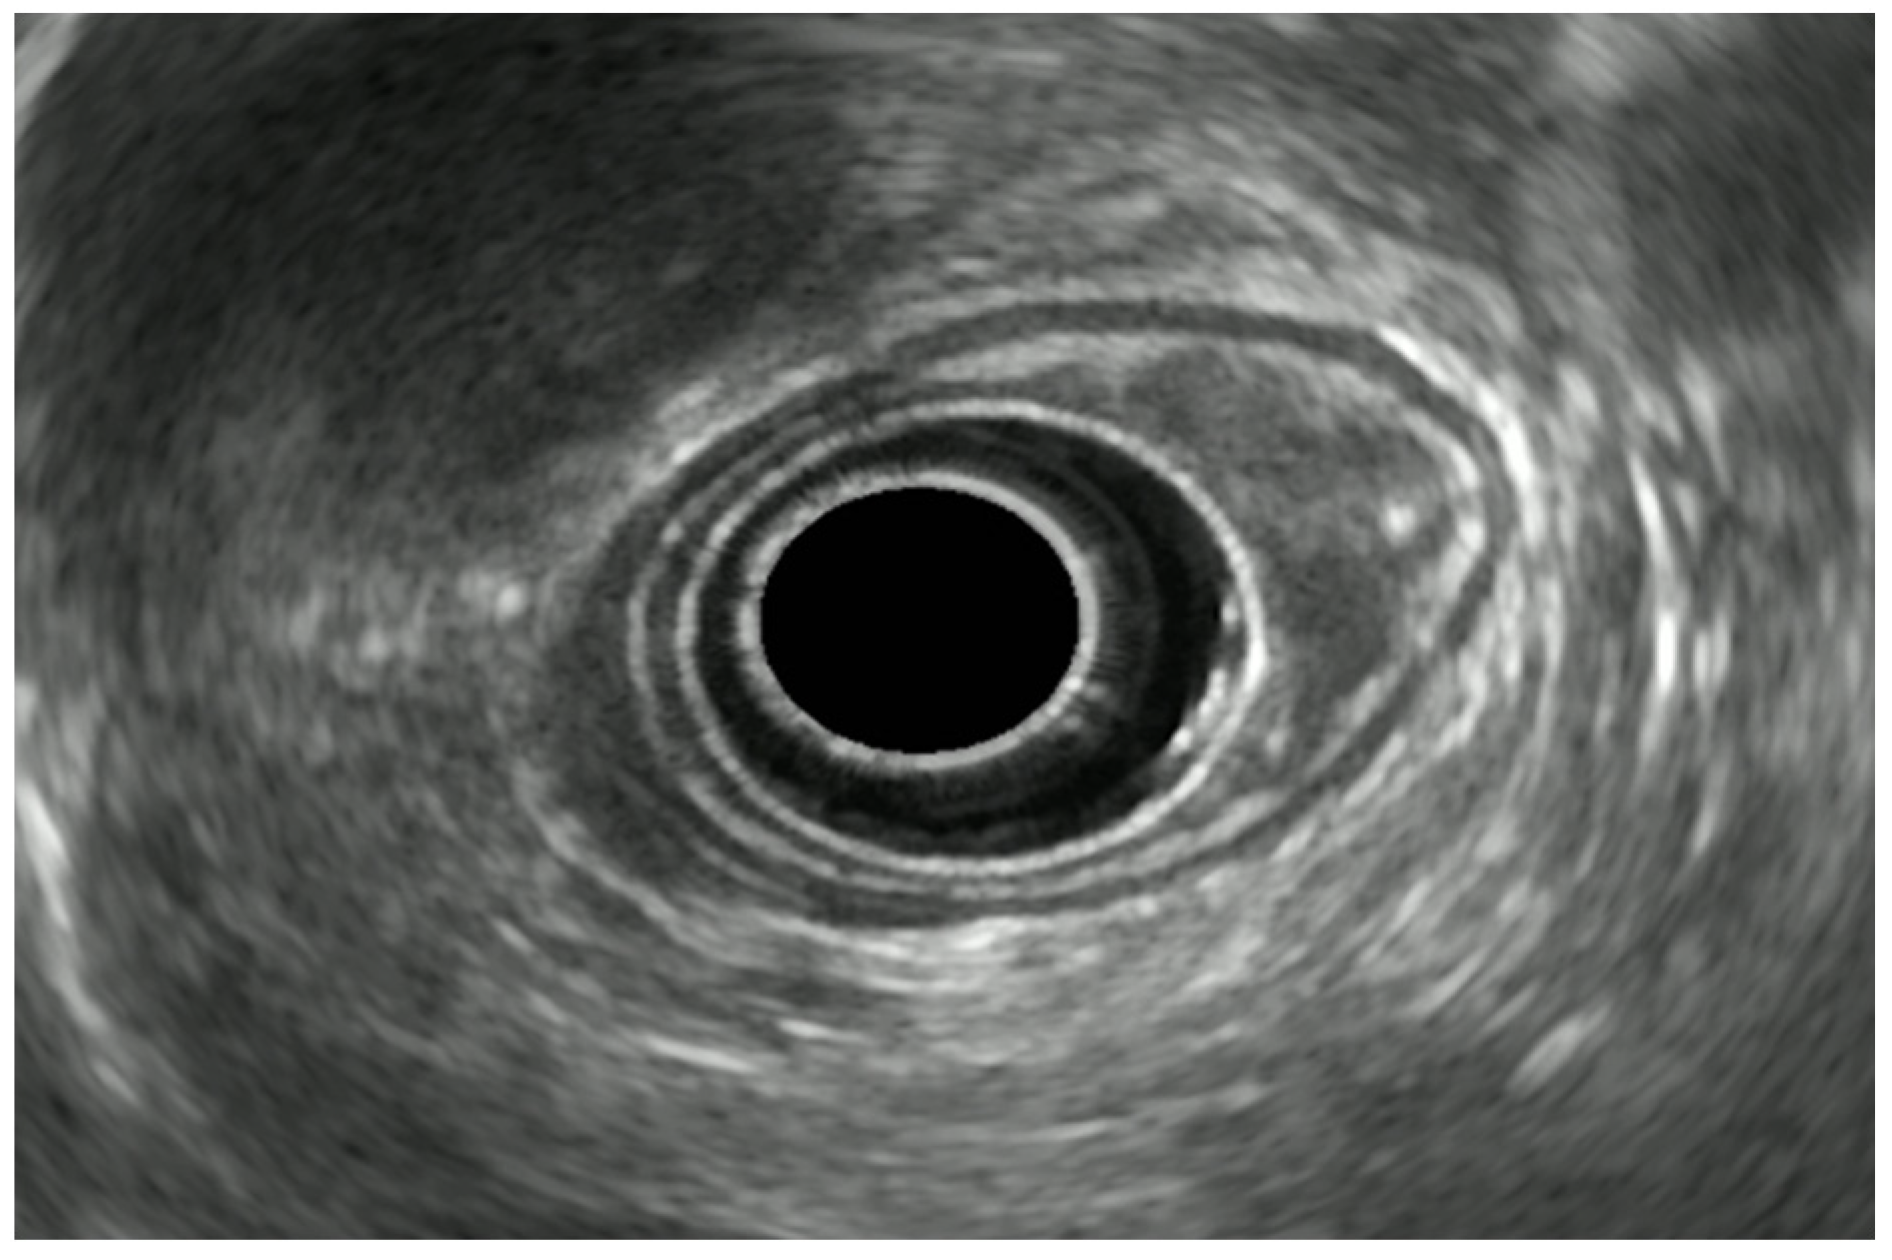

7. Endoscopic Rectal Ultrasound

8. Rectal Neoplastic Lesions

8.1. Rectal Superficial Cancer

8.2. Advanced Rectal Cancer